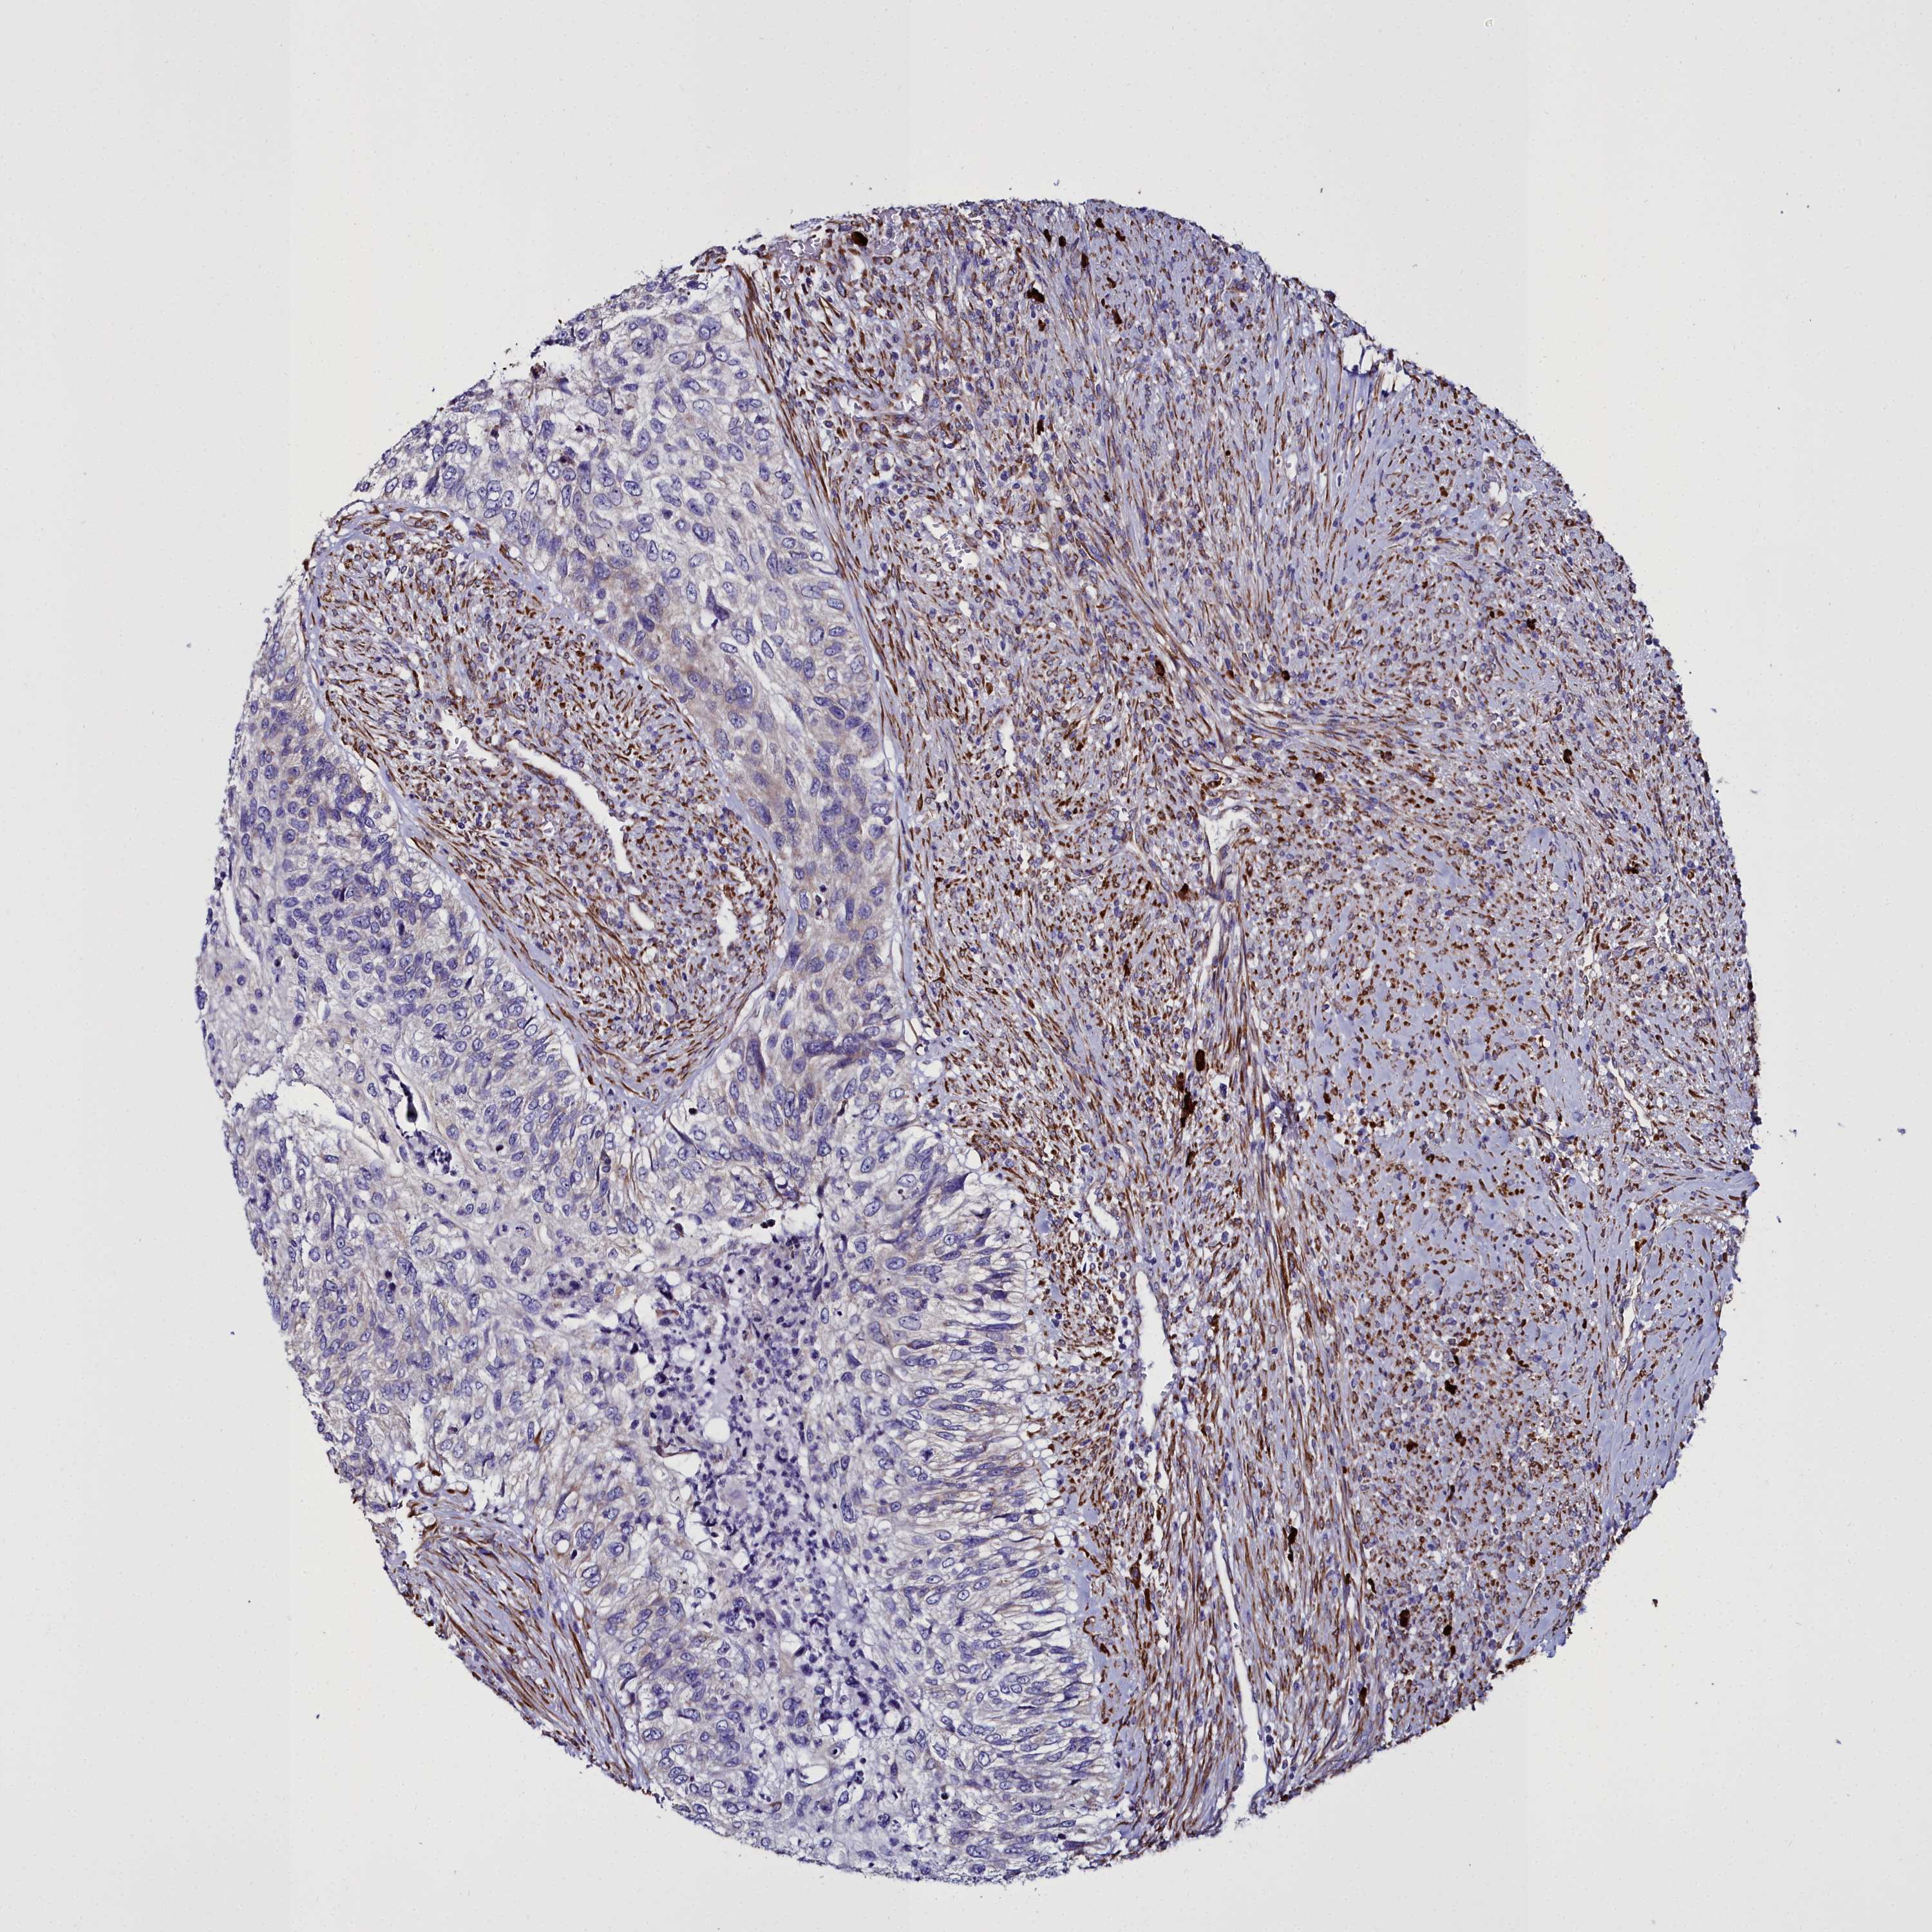

UROTHELIAL CANCER - Protein expressioni

A mouse-over function shows sample information and annotation data. Click on an image to view it in a full screen mode. Samples can be filtered based on level of antibody staining by selecting one or several of the following categories: high, medium, low and not detected. The assay and annotation is described here.

Note that samples used for immunohistochemistry by the Human Protein Atlas do not correspond to samples in the TCGA dataset.

Antibody stainingi

Antibody staining in the annotated cell types in the current human tissue is reported as not detected, low, medium, or high, based on conventional immunohistochemistry profiling in selected tissues. This score is based on the combination of the staining intensity and fraction of stained cells.

Each image is clickable and will lead to virtual microscopy that enables deeper exploration of all samples and also displays staining intensity scores, fraction scores and subcellular localization as well as patient and tissue information for each sample.

Antibody HPA034677

Antibody HPA034678

Staining

High

Medium

Low

Not detected

Intensity

Strong

Moderate

Weak

Negative

Quantity

>75%

75%-25%

<25%

None

Location

Nuclear

Cytoplasmic/membranous

Cytoplasmic/membranous,nuclear

Urothelial carcinoma, High grade